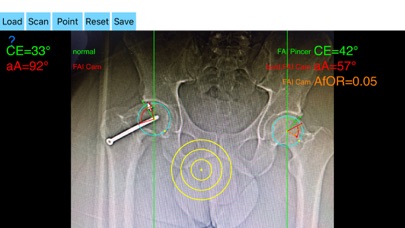

The drawn lines between points, allows app to estimate in radiographs, Center-Edge Angle (CE), α - angle (aA) and the anterior femoral offset ratio (AfOR). The measured values are compared with values from normal reference database. In case the measured angles are beyond the normal range, the hip is categorized as normal, dysplastic, borderline dysplastic hip and the type of femoroacetabular impingement (FAI) deformity namely cam type, pincer type or mixed is printed over the screen accordingly. Measures by the app are not affected by the X-ray projection.